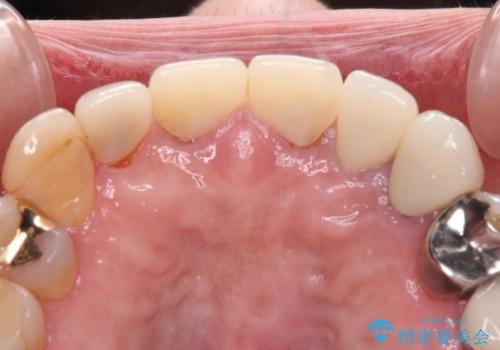

外れてしまったクラウンを保管しておき、新しいクラウン製作の際に技工所に送ることで、今までと同じような色合いに仕上げることができ、周囲のクラウンとバランスを取ることができます。